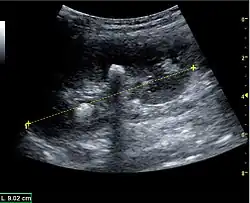

The length of the adult kidney is normally 10–12 cm, and the right kidney is often slightly longer than the left kidney. The adult kidney size is variable due to the correlation with body height and age; however, normograms for pediatric kidney size are available.[1]

Cortical thickness should be estimated from the base of the pyramid and is generally 7–10 mm. If the pyramids are difficult to differentiate, the parenchymal thickness can be measured instead and should be 15–20 mm (Figure 3). The echogenicity of the cortex decreases with age and is less echogenic than or equal to the liver and spleen at the same depth in individuals older than six months. In neonates and children up to six months of age, the cortex is more echogenic than the liver and spleen when compared at the same depth.[1]